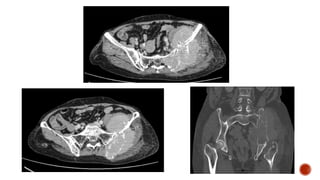

 There is fullness in the left side of the abdomen with the displacement of the bowel

loops to the right

 There are no calcifications

 The opacity is crossing the midline

 The lung fields are clear